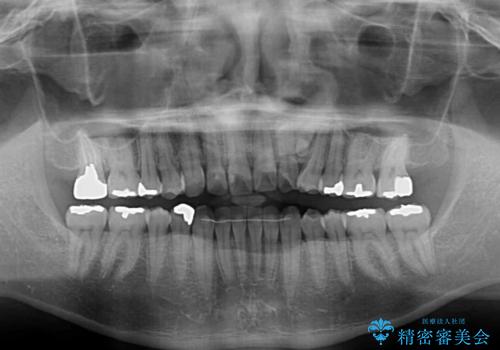

左上の犬歯が欠損しているため、正中の位置や奥歯の咬み合わせが理想的にならない点を了承していただきました。

インビザライン矯正は、1日22時間を目安に装着する必要がありますが、しっかりと装着してくださったので、順調に治療を進めることができました。